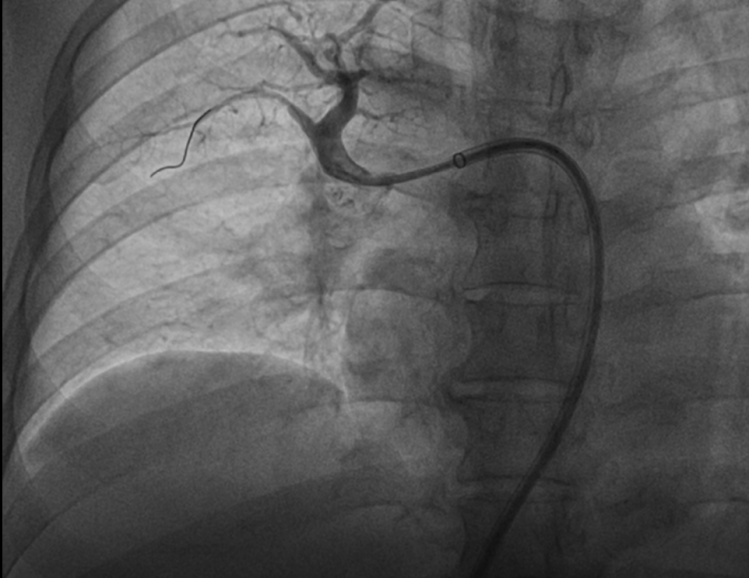

患者慕名至我院后,我科专家进一步对其进行了相关检查,最终诊断为:慢性血栓栓塞性肺动脉高压。心内科周亚峰副院长、陈弹主任、赵良平主任及团队成员进行深入讨论,并邀请呼吸科、血管外科与介入科等进行多学科(MDT)会诊,最终决定对其进行右心导管及肺动脉造影检查,结果提示肺动脉收缩压52mmHg,平均肺动脉压33mmHg,左右各肺动脉及其分支多发栓塞,可见多处血栓影及马赛克征。对右肺动脉A3、左肺动脉A1+2、左肺动脉A9行球囊扩张术,扩张后复查造影远端血流恢复良好。手术后患者的症状得到明显改善,心功能逐渐恢复,住院5天后平稳出院。出院后患者继续进行家庭氧疗、抗凝、利奥西呱降肺动脉压力等治疗,并密切随访中。随访至今,患者情况良好。

左肺动脉A1+2扩张前